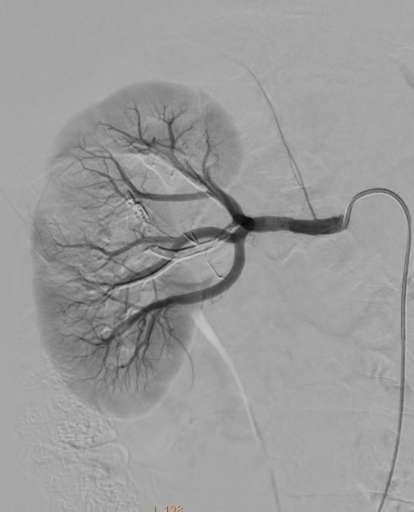

תמונות מההליך

שלבי הפעולה:

- הדגמת של הכליה וה-AML בכליה הימנית. הכליה נצבעת בחומר הניגוד בעצה רבה יותר מאשר ה-AML.